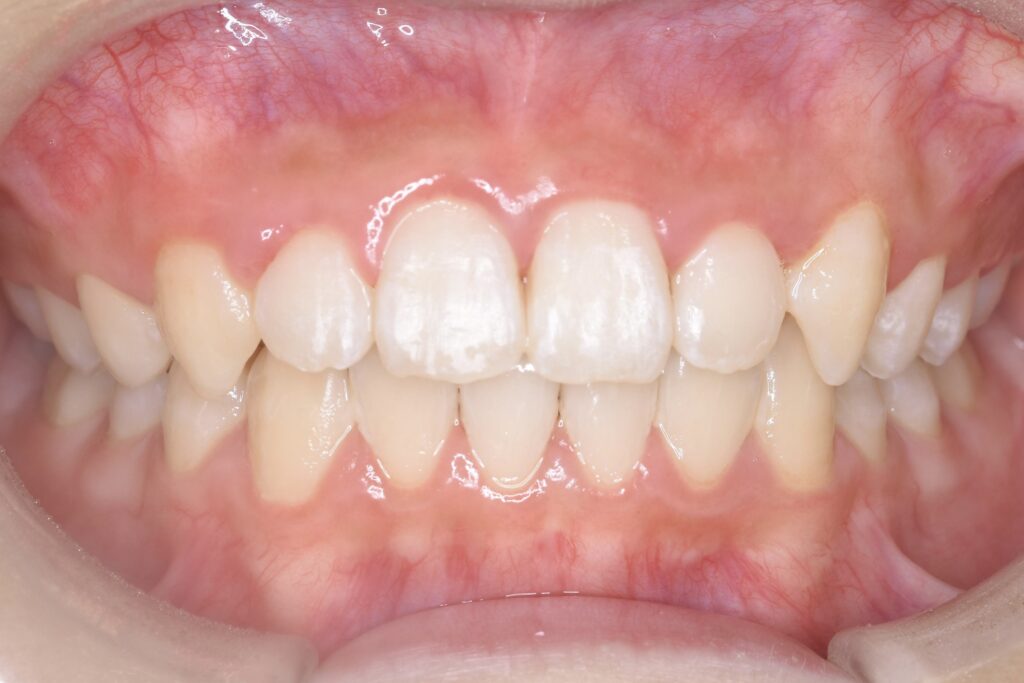

BEFORE

AFTER

主訴 通っている歯医者で矯正した方がいいと言われて気になっている。下の前歯がでこぼこしている。

診断名・主な症状 下顎前歯の叢生を伴う過蓋咬合

治療内容 上下の歯並びの幅を拡げつつ、前歯の関係を改善しました。